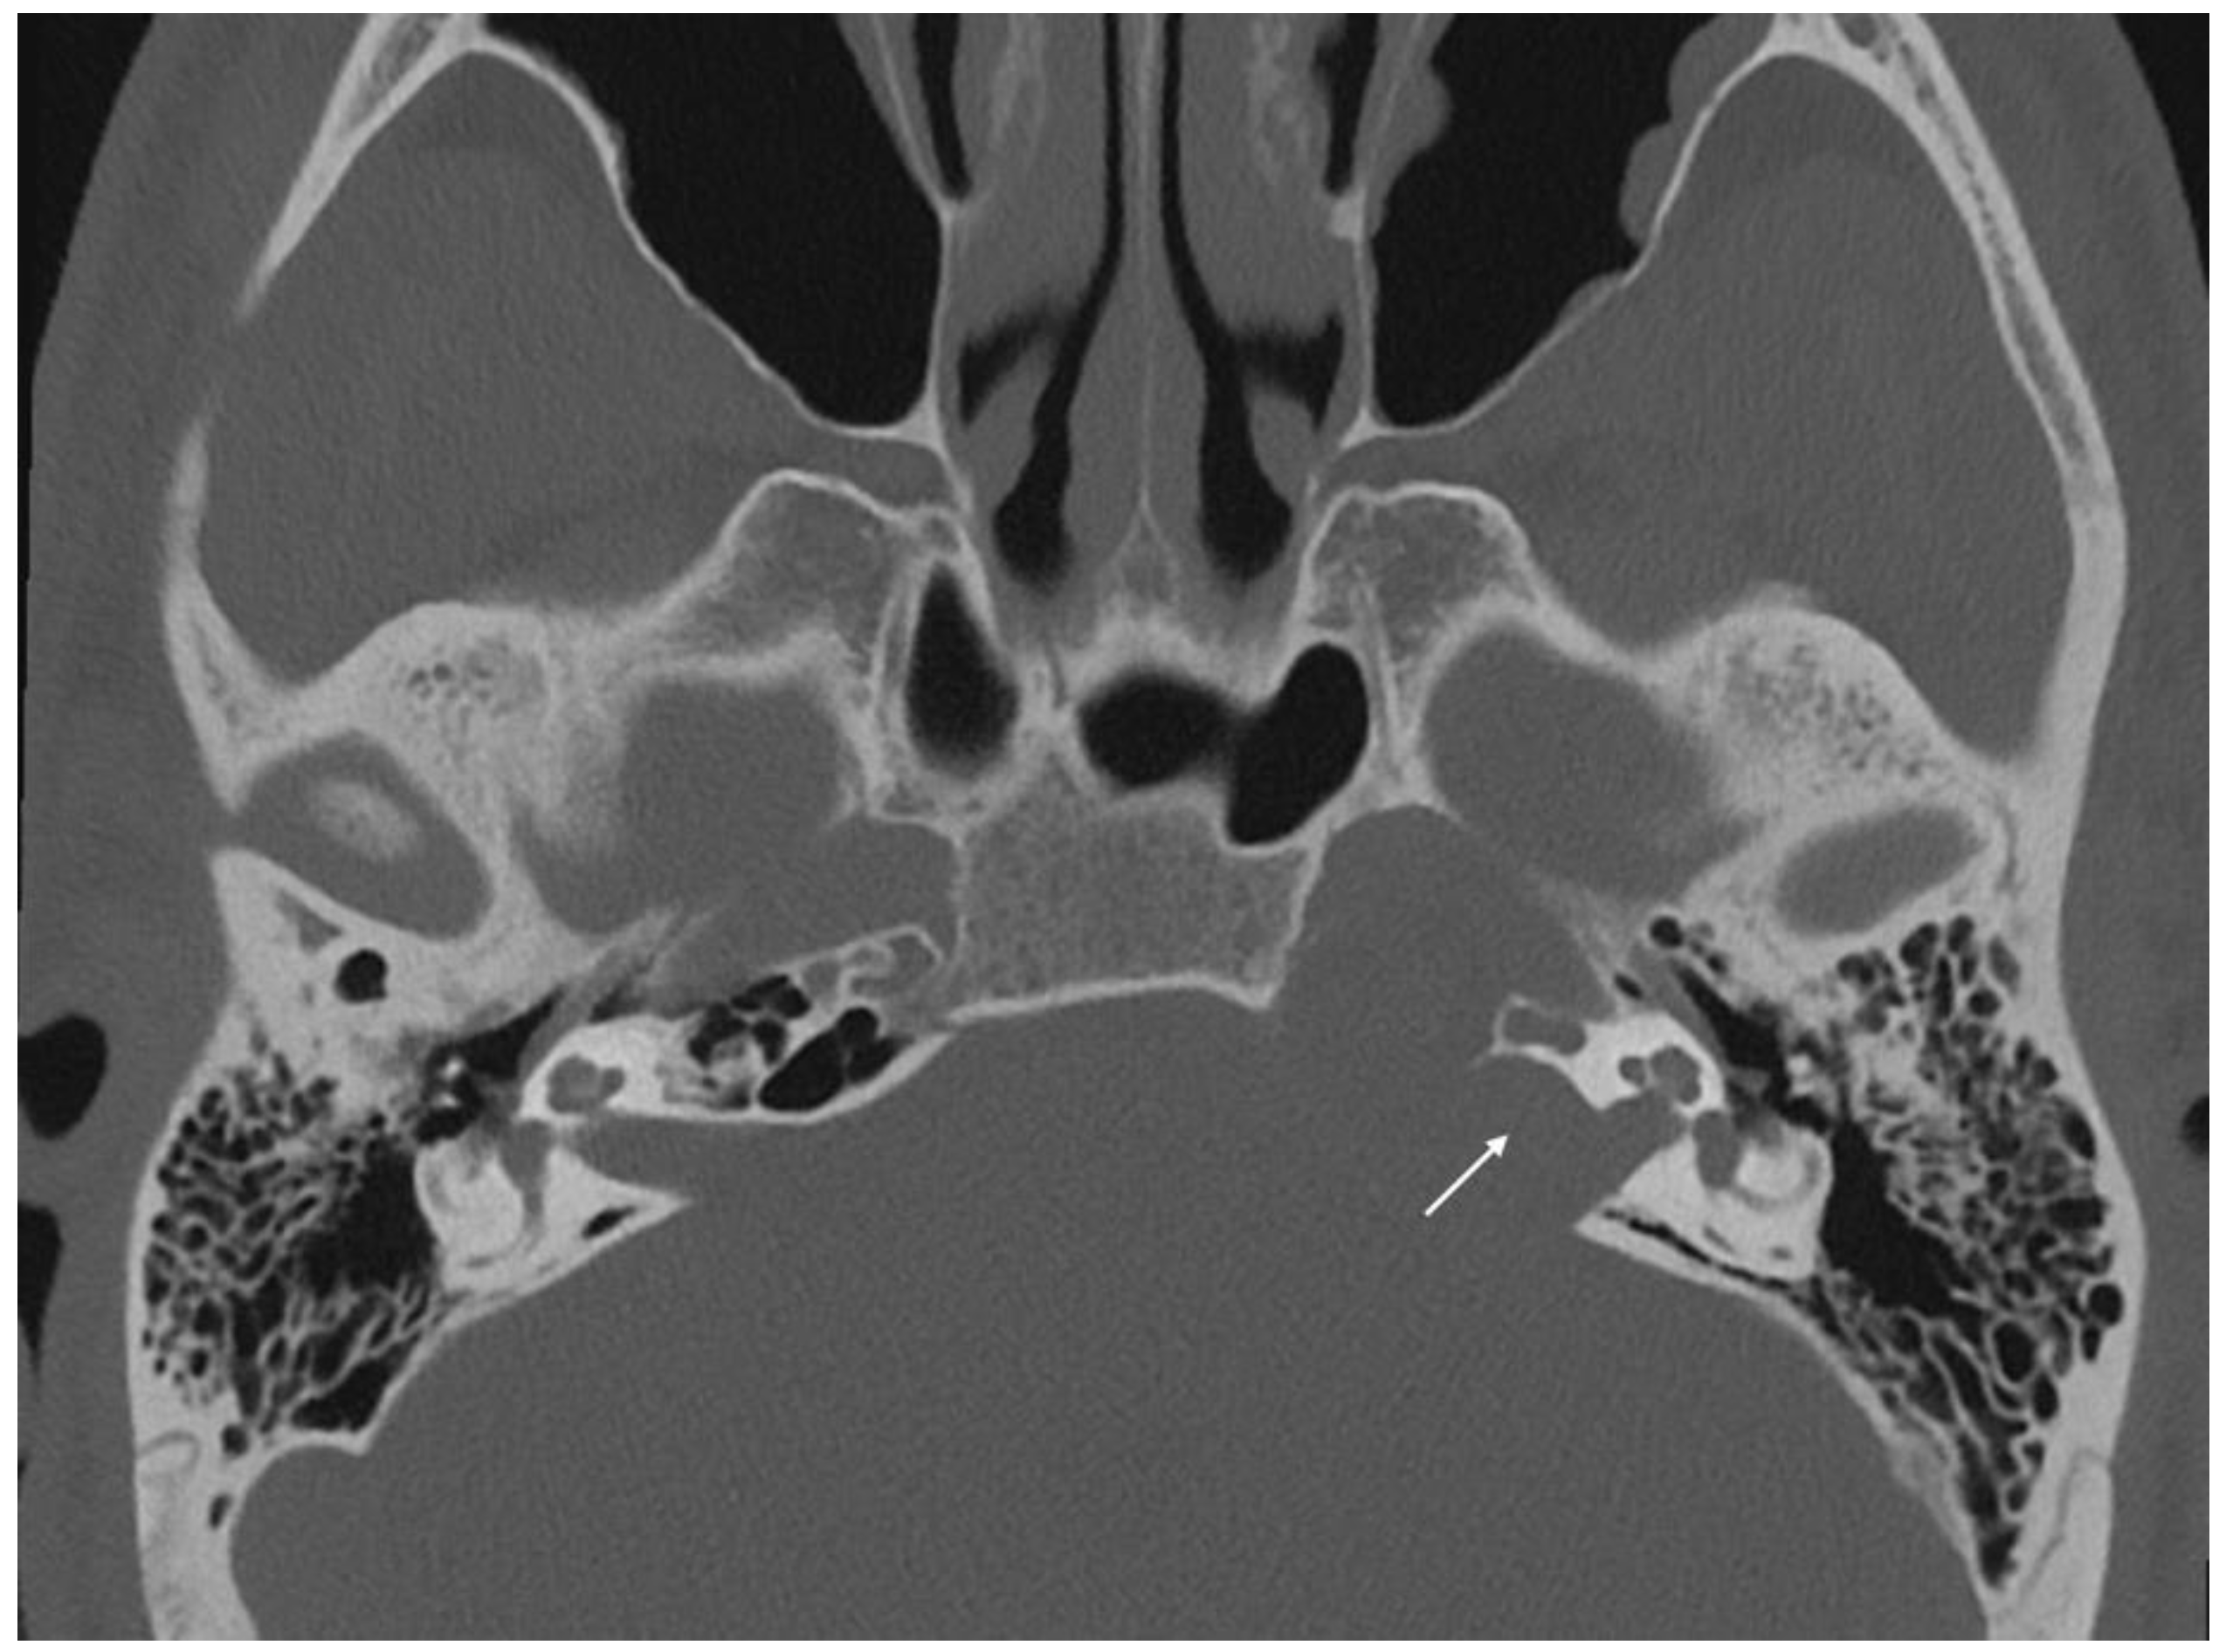

Imaging data from each patient were examined by an expert radiologist and an ENT specialist focusing attention not only on the location of the cyst, but also on the adjacent structures involved. Considering the available literature on symptoms and hypothesized regions of radiological involvement, we established a reproduceable pre-operative radiologic map to better correlate typical symptoms, such as headache, hearing loss, vestibular symptoms, tinnitus, otitis media, diplopia, and facial paresthesia, with PACG. The following regions were considered: (1) temporal lobe/posterior fossa compression (Figure 1); (2) Meckel’s cave compression (Figure 1); (3) Eustachian tube compression/erosion (Figure 2); (4) internal auditory canal erosion (Figure 3); (5) cochlear basal turn erosion (Figure 4); (6) Dorello canal involvement (Figure 5); (7) jugular tubercle erosion. The latter parameter was introduced to evaluate its possible correlation with an atypical clinical presentation, namely fainting. To standardize all these radiological examinations, the jugular tubercle was defined in axial sections as the bony convexity medial to the jugular foramen just above the hypoglossal canal; in coronal sections, it is the bony part directly above the hypoglossal canal (Figure 6).

Figure 2. Axial CT scan showing compression of the Eustachian tube by a cholesterol granuloma (white arrow).